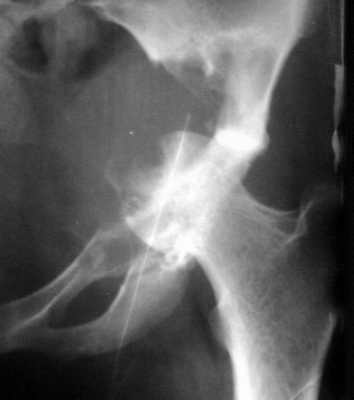

Женщина 22 лет поступила с протрузией вертлужной впадины.Рентгенограммы (1, 2) с интервалом в 1 год. В онкодиспансере сделали биопсию - ОБК без малигнизации. Какой объем операции здесь следует предпринять? Есть ли какие-то шансы на первичное эндопротезирование? Где такие операции делают? В том числе в Европе. Заранее спасибо.

The xray appearance is consistent with a bengin aggessive or malignant lesion involving both the acetablum and the femoral epiphysis (there appears to be erosions of the femoral head). The differential diagnosis would include non-tumor conditions such as Brown's tumor (a serum calcium should be measured), benign aggressive lesions such as GCT, ABC and chondroblastoma, and malignant lesions such as telangiectatic osteosarcoma and MFH of bone.

However, the extent of the tumor in the pelvis and lack of a cortical rim leading to a large uncontained defect would be too much bone loss for any type of acetabular reconstruction.

A wide resection with reconstruction with a saddle modular prosthesis would be an option depending on the status of the remainder of the ilium.

looking to the X-rays and CT scan it appears this young lady has an aggressive bone leasion.

The X-ray and CT scan appearance is likely as the chondrosarcoma what is seldom but common

finding in the replacement surgery of the hip. Having precise histological, CT and MRI data should be planed the amount of surgery after detailed discussion with patient. There is no any possibility to perform primary replacement. If there is the chondrosarcoma hemipelvectomy would be the most live saving procedure. If there is an aggressive giant cell tumor or other findings about allografting, reconstructive surgery with custom made implant or saddle modular prostheses (W.Link) could be discussed. In other wards there are so many different thinks what should be discussed with patient